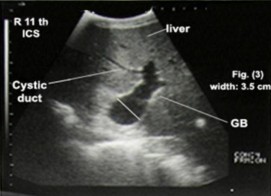

胆囊在肝脏腹内侧成像,并与颅十二指肠密切相关,它表现为黑色囊肿(充满液体的囊泡),管腔无回声,边缘有细小的回声,呈梨形。胆囊管在纵向截面上成像为细长的无回声结构,具有回声壁,在横截面上成像为管状无回声结构,在截面上具有回声壁(看下图)。